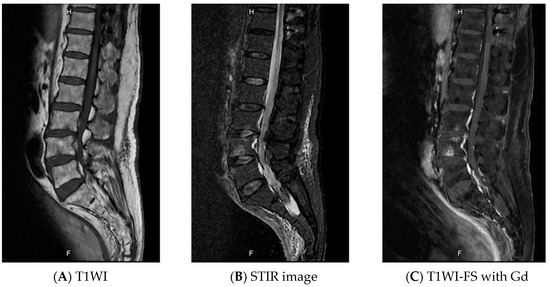

Lumbosacral plexopathy was initially diagnosed, caused by infection or lymphoma involvement. A lumbar puncture was performed and xanthochromic CSF was found. Cerebrospinal fluid analysis revealed a white blood cell count of 2 cells/mm3, a protein concentration of 2181 mg/dl, and a glucose concentration of 57.9 mg/dl (concurrent a blood glucose concentration of 115 mg/dl). Gram stain, Ziehl–Neelsen stain, Indian ink preparation, cryptococcal antigen, and culture were all negative. The CSF culture, which was subsequently reported, was also negative for M. tuberculosis. Adenosine deaminase levels in the CSF will help in determining the presence of central nervous system tuberculosis, which was determined by an automated method, were 30.9 U/L. Cytopathological and flow cytometric analysis of the CSF demonstrated no evidence of malignant lymphoma. Due to the patient’s high CSF protein concentration but normal cell count (Froin’s syndrome), magnetic resonance imaging (MRI) of the lumbo-sacral (LS) spine was performed to rule out a spinal cord compression, and it showed a 4.5 × 1.5 cm intramedullary expanding lesion at the T12-L1 level. The lesion was isointense on T1-weighted and hyperintense on T2-weighted and short tau inversion recovery (STIR) images, and exhibited enhanced homogeneously after contrast administration. Diffuse spinal cord edema above the lesion was also detected (Figure 1). The results of a chest X-ray were within the normal limits. Anti-HIV was non-reactive. A T12-L1 laminectomy was performed, revealing an enlarged conus with an irregular surface. The nerve roots appeared normal. A right-side myelotomy and multiple punch out biopsy were performed. Histopathology of the tissues revealed mild reactive gliosis. Neither granuloma nor a tumor was found then Ziehl–Neelsen stain and tissue culture for M.tuberculosis were not performed. After the operation, the patient suffered from urinary retention, which did not resolve.

In cases such as these, MRI is the optimal method of investigation, as it is both sensitive and noninvasive. The MRI features of IMT can vary depending on the stage of tuberculoma formation (noncaseating, caseating with a solid center, and caseating with a liquid center). In its earliest stage (noncaseating), tuberculoma is characterized by severe inflammatory reaction with poor formation of the collageneous capsule. T1-weighted images show isosignal or slightly hyposignal intensity, and T2-weighted images show hypersignal intensity. The granuloma exhibits homogeneous enhancement after contrast administration on T1-weighted images. Later during the caseating stage, collagen becomes richer in the surrounding capsule, and rim enhancement becomes visible on an MRI after contrast administration. A solid caseating tuberculoma appears iso- to hypointense on T1-weighted images and hypointense center with an iso- to hyperintense rim on T2-weighted images. When the solid center of the caseating tuberculoma liquefies, T1-weighted images show hyposignal intensity and T2-weighted images show hypersignal intensity at the center with a hypointense rim [23] However, these findings are not specific to tuberculoma. The differential diagnoses for space-occupying lesions of intramedullary conus medullaris can be based on the presence of spinal intramedullary tumors (astrocytoma, ependymoma, metastasis, lymphoma) and granulomatous inflammations.

Figure 1. Magnetic resonance imaging of the lumbosacral spine revealed a 4.5 × 1.5 cm intramedullary expanding lesion at the T12-L1 level. The lesion exhibited isosignal intensity on the T1-weighted image (A) and hypersignal intensity on the Short tau inversion recovery (STIR) image (B) with homogeneous enhancement (C). Hypersignal intensity of the spinal cord above the lesion was also detected on the STIR image (B), which represented diffuse spinal cord edema.